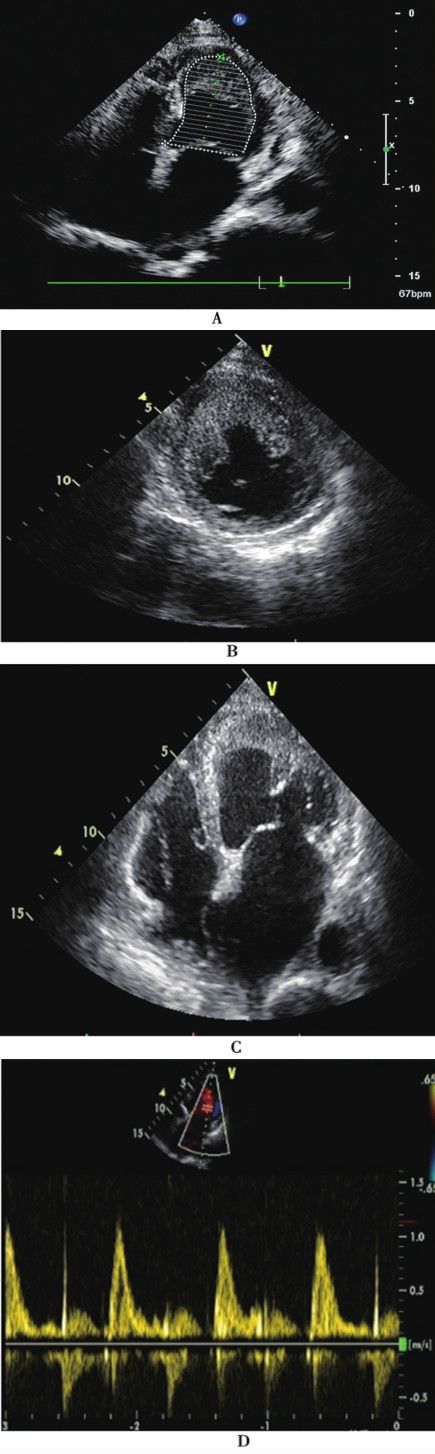

经胸超声心动图(tte)显示:左心室射血分数降低(lvef 30%),前壁,室间隔

3月22日,超声心动图:左心房前后径41mm,左心室舒张末期内径54mm,左